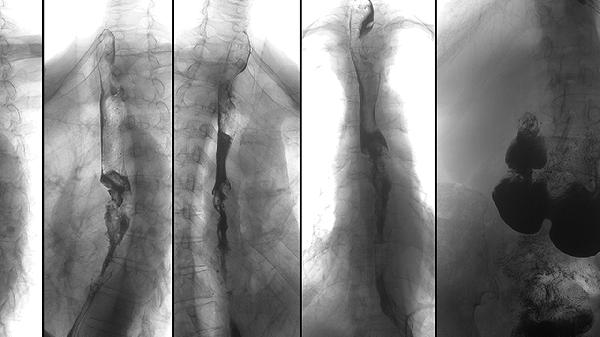

先天性成骨不全主要由COL1A1或COL1A2基因突變引起,這些基因負責(zé)編碼膠原蛋白,膠原蛋白是骨骼的重要組成部分。突變導(dǎo)致膠原蛋白結(jié)構(gòu)異常,骨骼強度下降。治療方法包括藥物治療,如雙膦酸鹽類藥物,可以增加骨密度;基因治療正在研究中,尚未廣泛應(yīng)用;對于嚴重病例,可能需要手術(shù)干預(yù),如髓內(nèi)釘固定術(shù)。

先天性成骨不全患者的骨骼生長速度較慢,容易出現(xiàn)畸形。治療方法包括物理治療,如水中運動,可以增強肌肉力量;佩戴支具,如脊柱矯形器,可以預(yù)防脊柱側(cè)彎;手術(shù)治療,如截骨術(shù),可以糾正骨骼畸形。